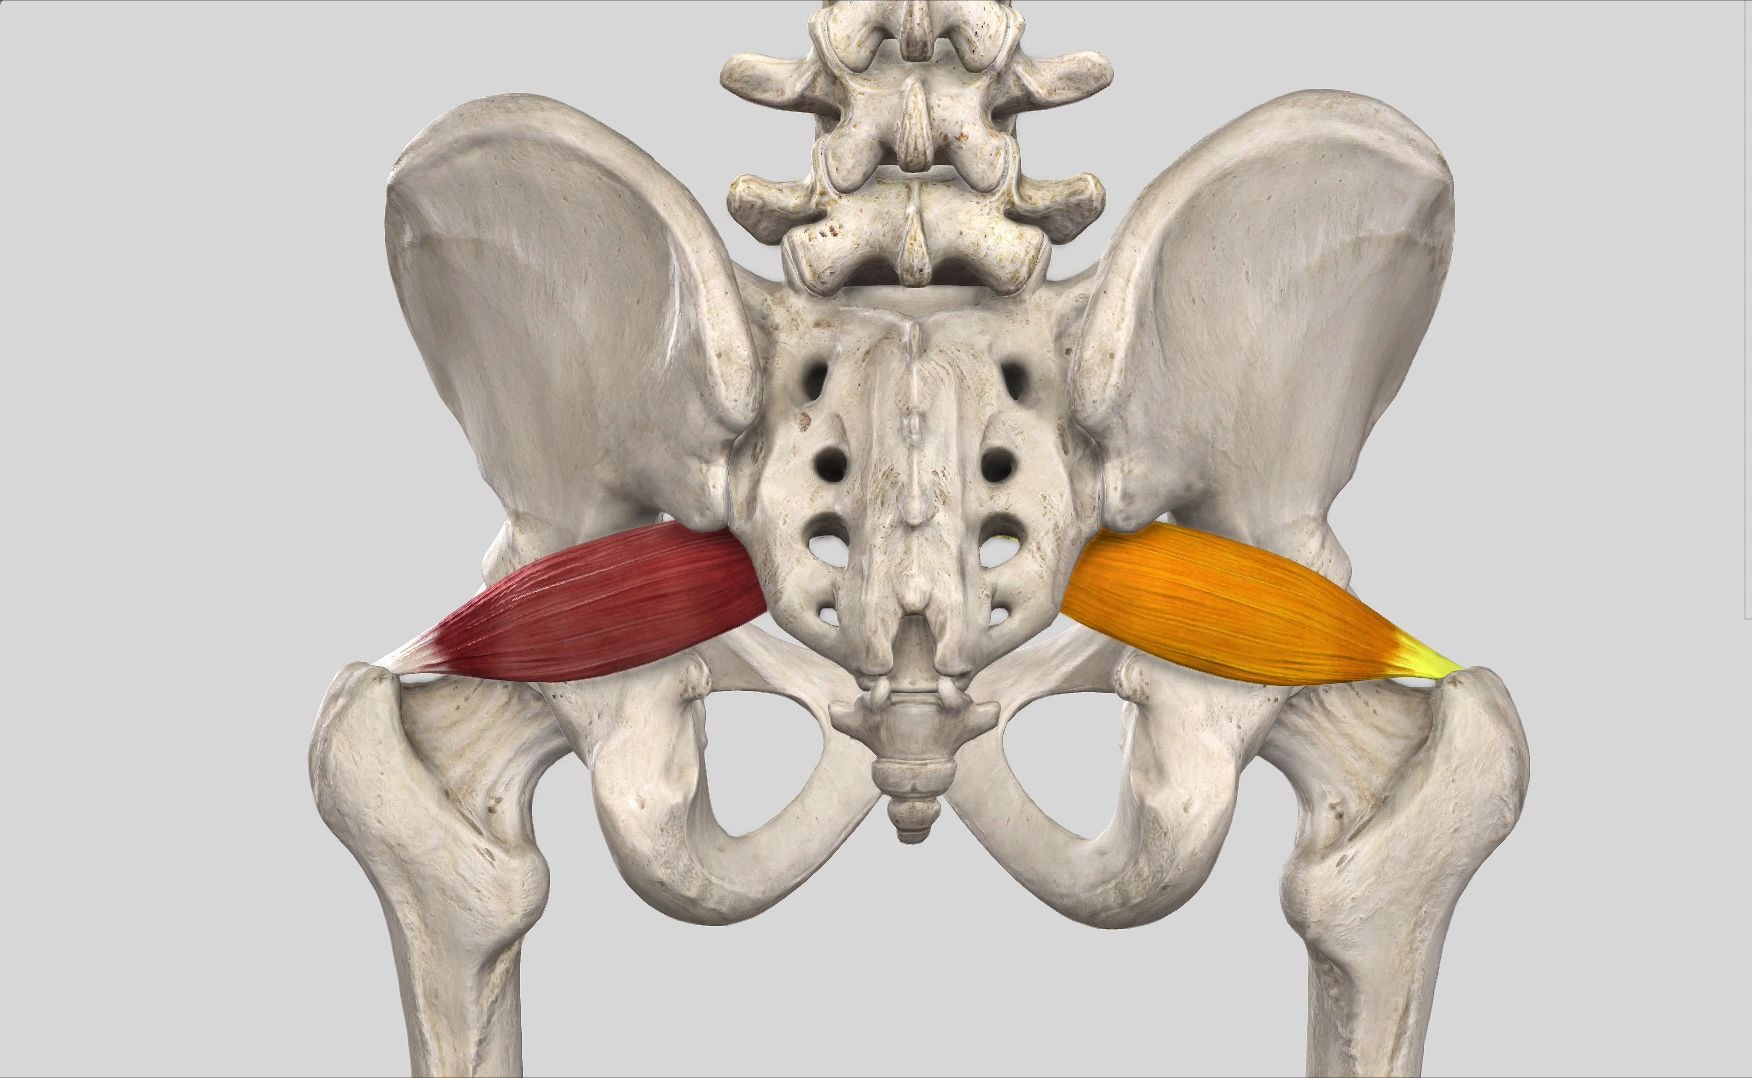

【每日一肌】梨状肌——坐骨神经痛的必要之肌!

图片尺寸1752x1078